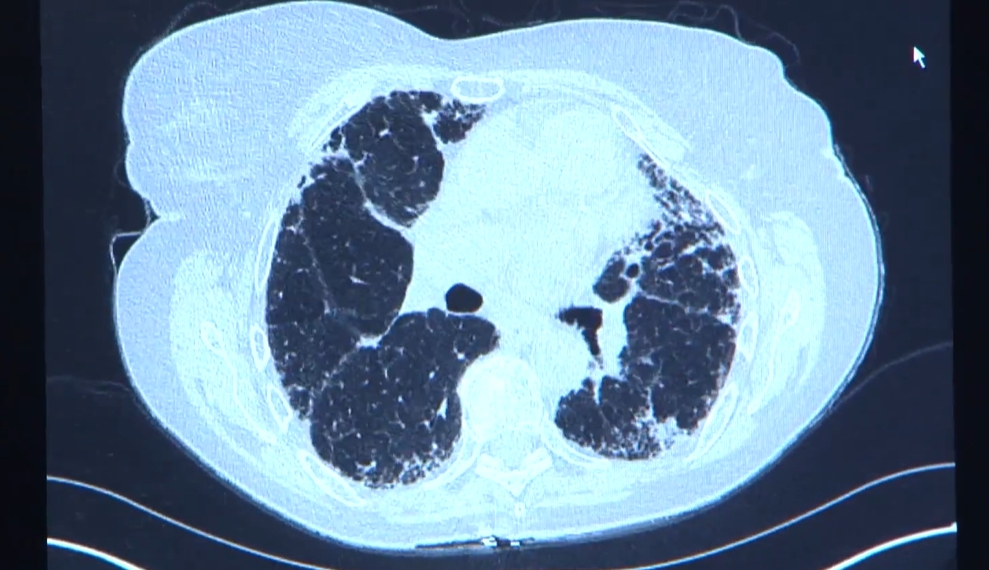

✔ 흉부 CT에서 이상 소견이 나온 경우